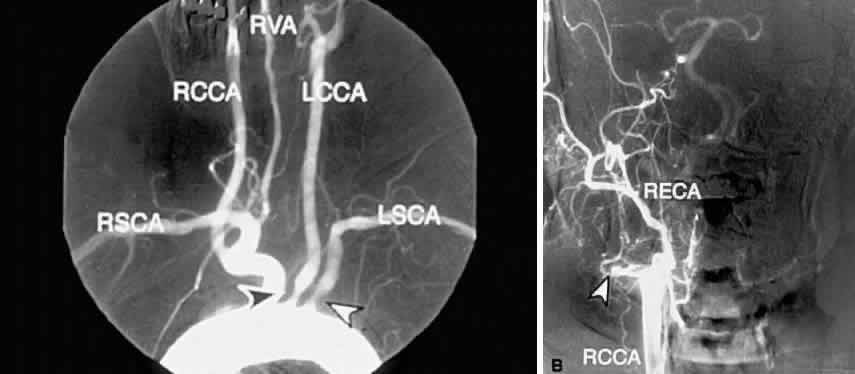

Carotid angiography is performed by selective common carotid arterial injection of a radiopaque contrast dye via transfemoral catheterization. In the traditional technique, the image of the inner luminal silhouette is produced on x-ray emulsion (Fig. 10A and B). More recently, digital images and computerized image enhancement have improved resolution and reduced the amount of contrast dye required.46,47 This method can detect ulcerative lesions, severe stenosis, and formation of mural thrombus. It can also demonstrate collateral circulatory patterns.

Fig. 10. A. Digital subtraction aortogram revealing a 90% atherosclerotic stenosis of the proximal left common carotid artery (black arrowhead) and 80% stenosis of the proximal left subclavian artery (white arrowhead). RSCA, right subclavian artery; RCCA, right common carotid artery; RVA, right vertebral artery; LCCA, left common carotid artery; LSCA, left subclavian artery. B. Digital subtraction angiogram with a right common carotid injection from the same patient. There is complete occlusion of the right internal carotid artery due to atherosclerosis (white arrowhead). The right external carotid artery (RECA) and the right common carotid artery (RCCA) fill normally.